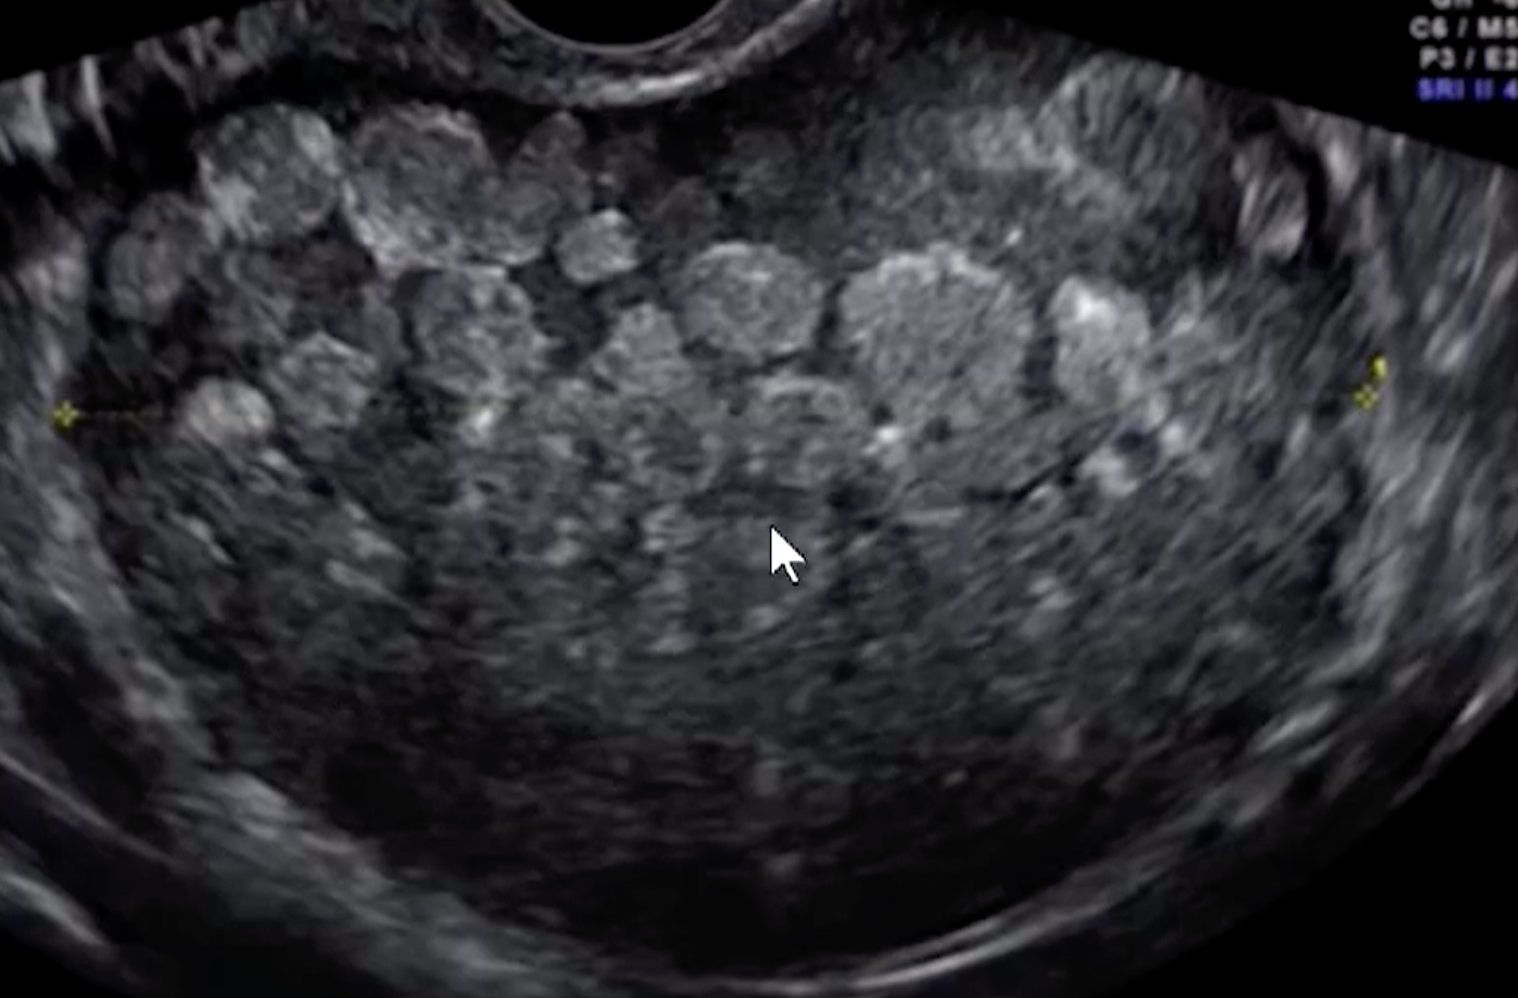

• Has a cobweb appearance - US below

• Retractable clot (left thick arrow in US below)

• No color on doppler